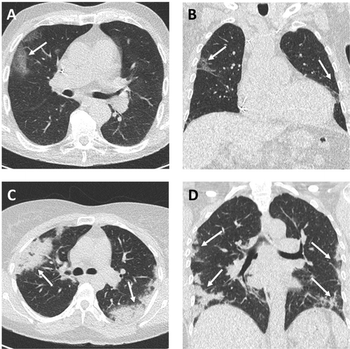

COVID-19 and other viral infections have unique imaging characteristics that can help with diagnosis, experts say.

Expert panel developed six-category system to classify chest CTs and streamline structured reporting around COVID-19.